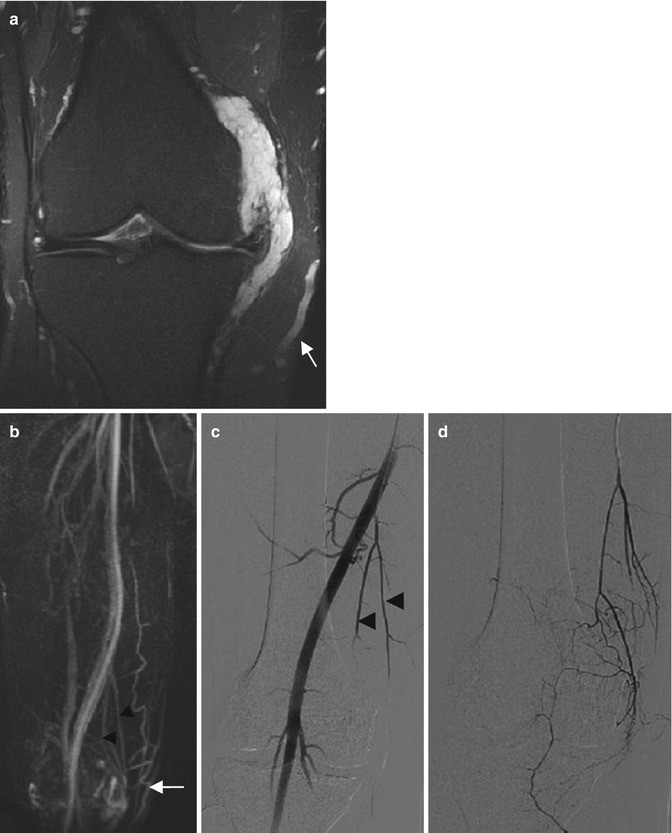

Arteriovenous malformation of the knee in a 30-year-old man. (a) Coronal T2-weighted MR image with fat suppression. (b) Maximum intensity projection (MIP) after 3D contrast-enhanced MR angiography. (c, d) Conventional angiographic images acquired during early arterial phase before the treatment. (a) The lesion is composed of tortuous enlarged feeding arteries located within the medial collateral ligament with a distended vein. (b) Two feeding arteries (black arrowheads) are seen on MIP after 3D contrast-enhanced MR angiography, with the early venous feeding (arrow). (c, d) Conventional angiographic images confirm these findings and reveals the two feeding arteries (arrowheads) from the superficial femoral artery